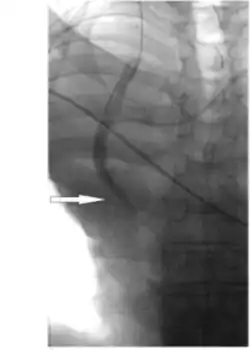

_(1)_(1).png)

Hydrophilic catheter treatments can also be used through placement of the catheter through the femoral veins to access the stenosis in the vena cava to measure haemodynamic and angiography. [6] Angiography allows for visualisation of the stenosis in the vena cava and measurements of the pressures and length of narrowing can be obtained from the technique, including the narrowest diameter of the stenosis. [6] Balloon angioplasties can also be performed in the narrowed vena cava using Sterling balloons. [6] Dilations are also performed with higher pressure Dorado balloons, using the same wire as the Sterling balloon. [6] Sustained results of increased flow and significant reduction in obstructions following stent implantation occurs from balloon angioplasty treatments. [6]